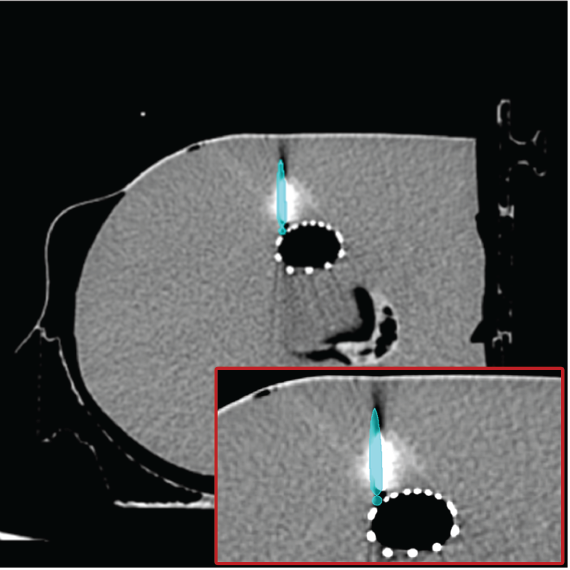

3.4 Phantom experiments

A phantom targeting experiment was conducted to evaluate the accuracy of needle insertion. Fig. 9A shows the experimental setup, including an endoleak phantom, an FG mounting frame, and a Canon Alphenix C-arm (Canon Inc., Tokyo, Japan). Three magnetically tracked needles were inserted into the endoleak phantom. During 2D navigation, the tracked needles (red lines) were projected on the fluoroscopic image, while the actual needles appeared as dark lines. The discrepancies between the two were used to quantify 2D targeting accuracy.

Fig. 9B illustrates the 3D navigation, including 3D reformations, the rendered contrast-enhanced CT volume, and tracked needles. To validate 3D needle insertion accuracy, we acquired a post-insertion non-contrast CT image (Fig. 9C). The inserted needles were clearly visible in three orthogonal views, with the 3D view displaying the inserted needles in silver and the tracked needles in cyan. Needle tip and angle errors were calculated by comparing the tracked needles with their segmented counterparts from the CT image. This process was repeated three times, with a total of nine inserted needles. The overall needle insertion errors were for the tip, and for orientation, as shown in Table 5.